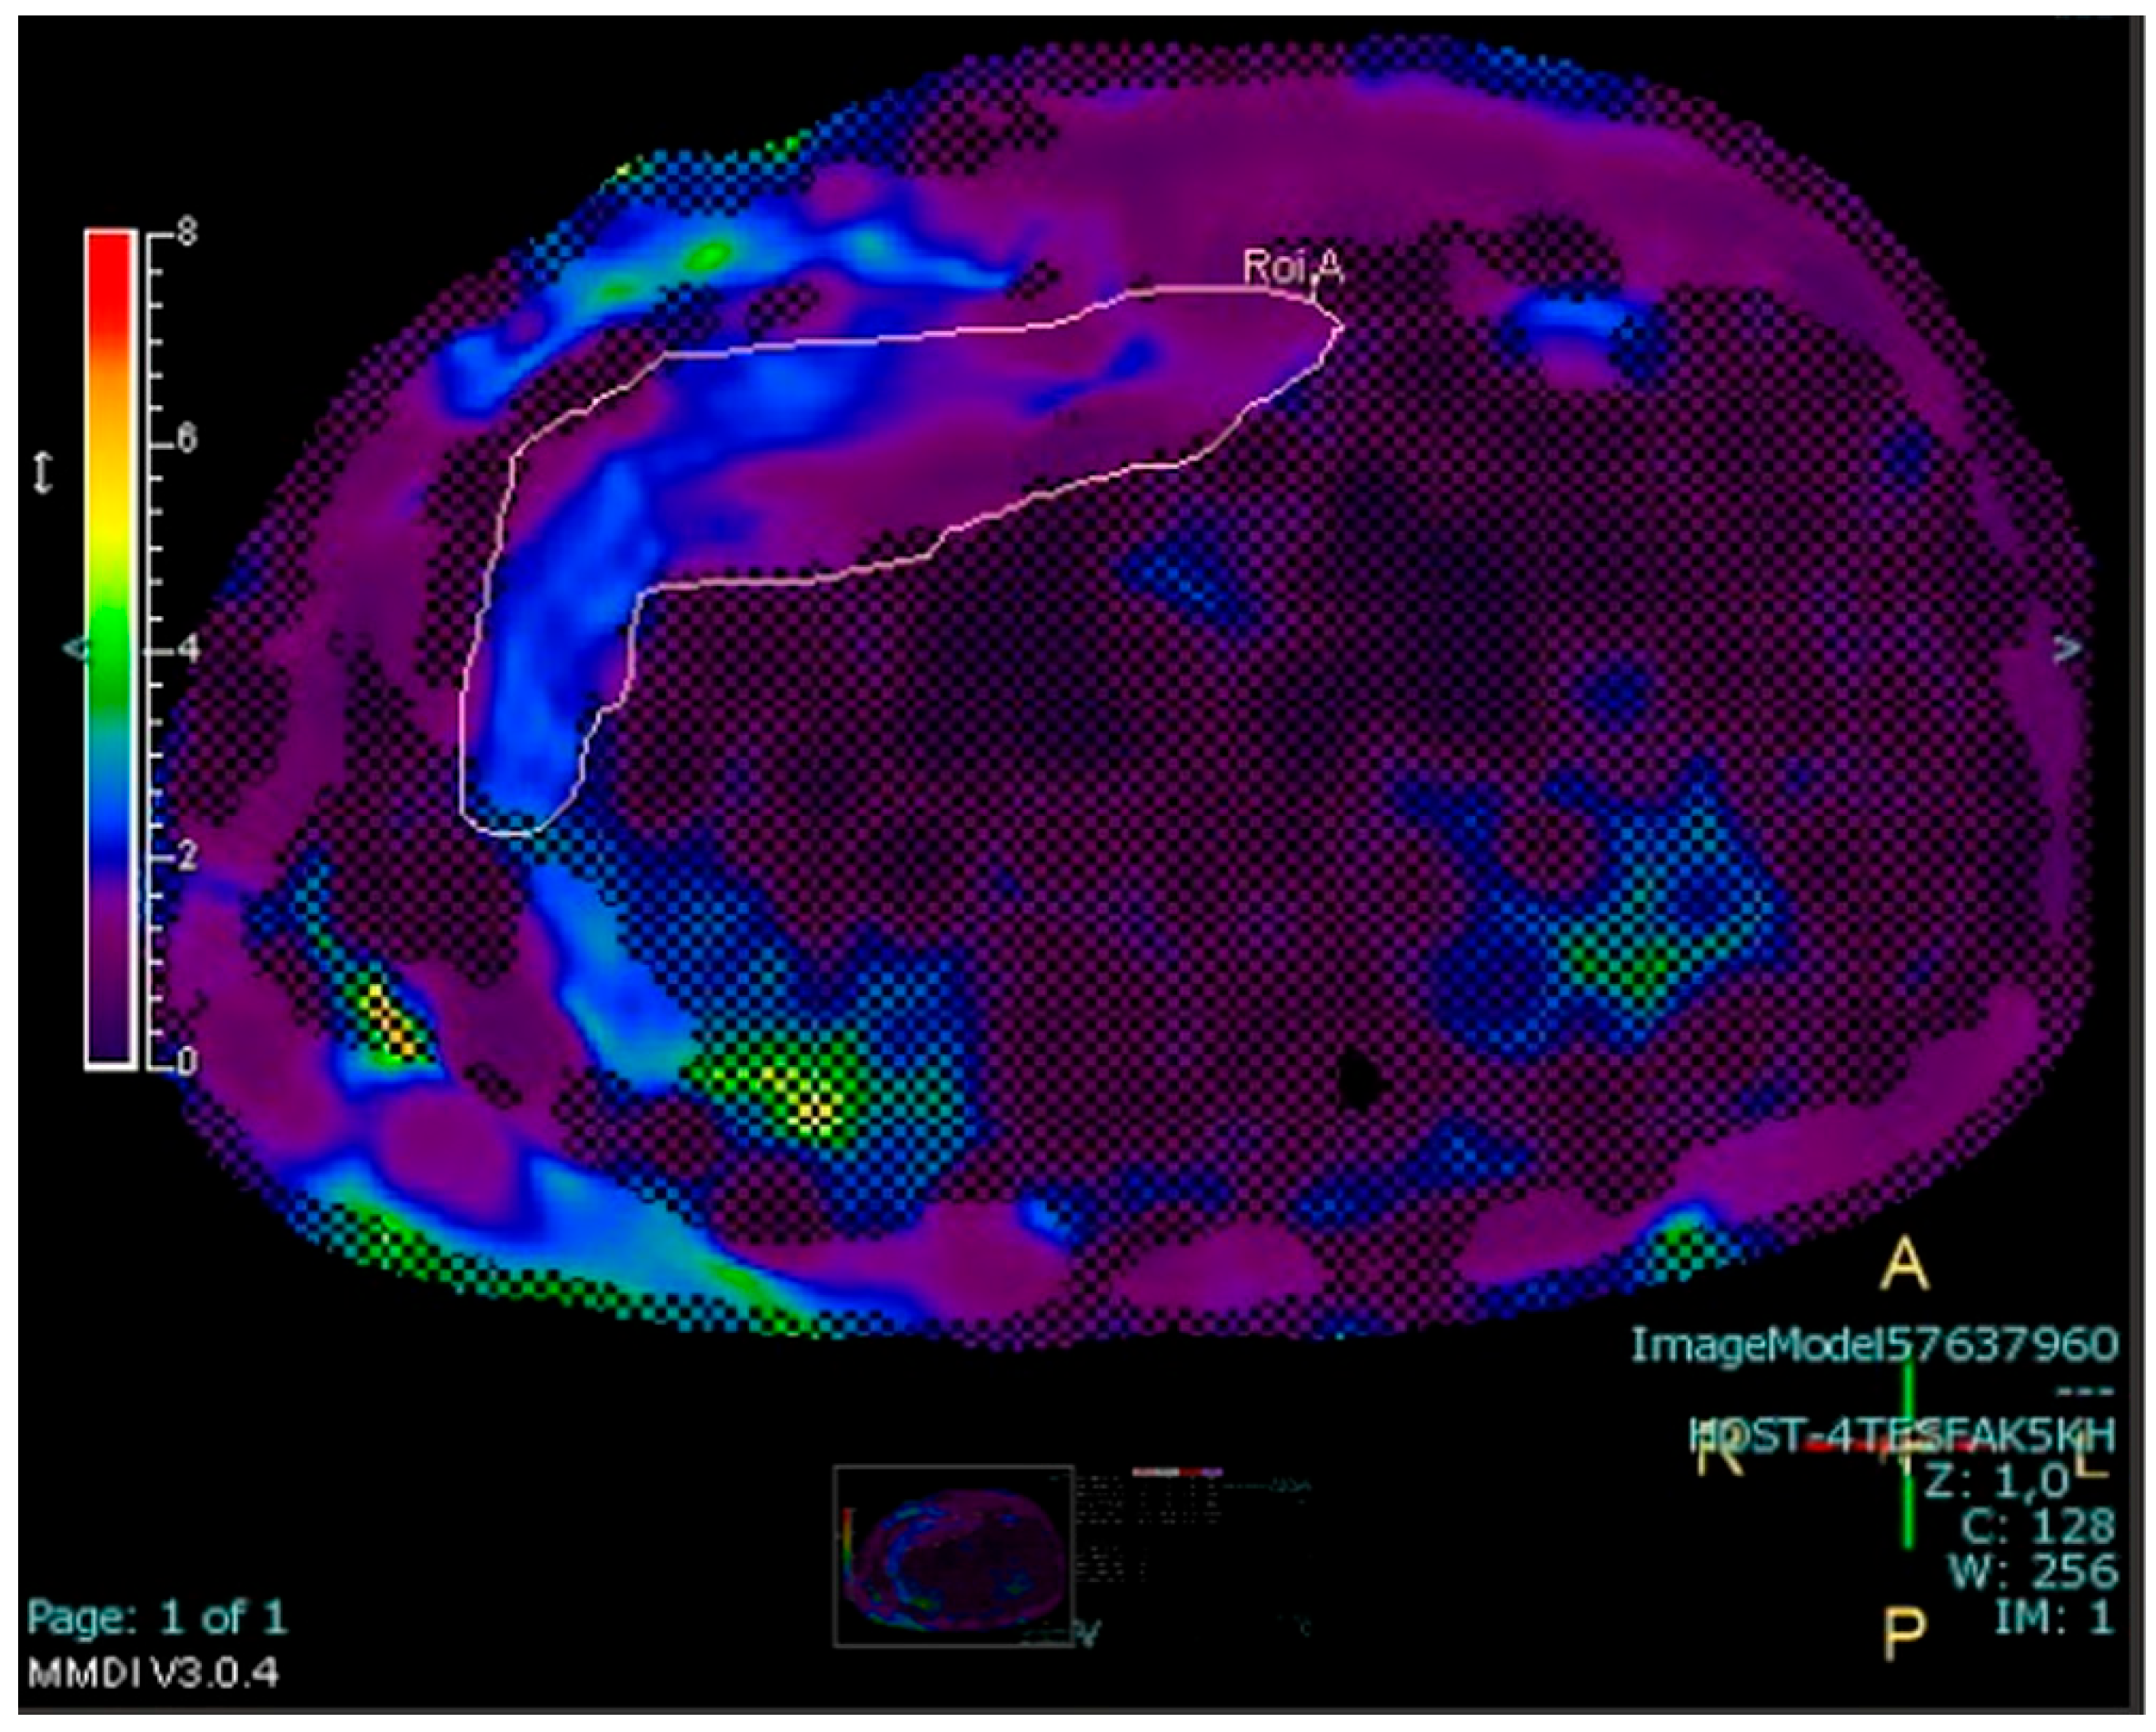

2.4.3. Measurement of Abdominal Fat Stores